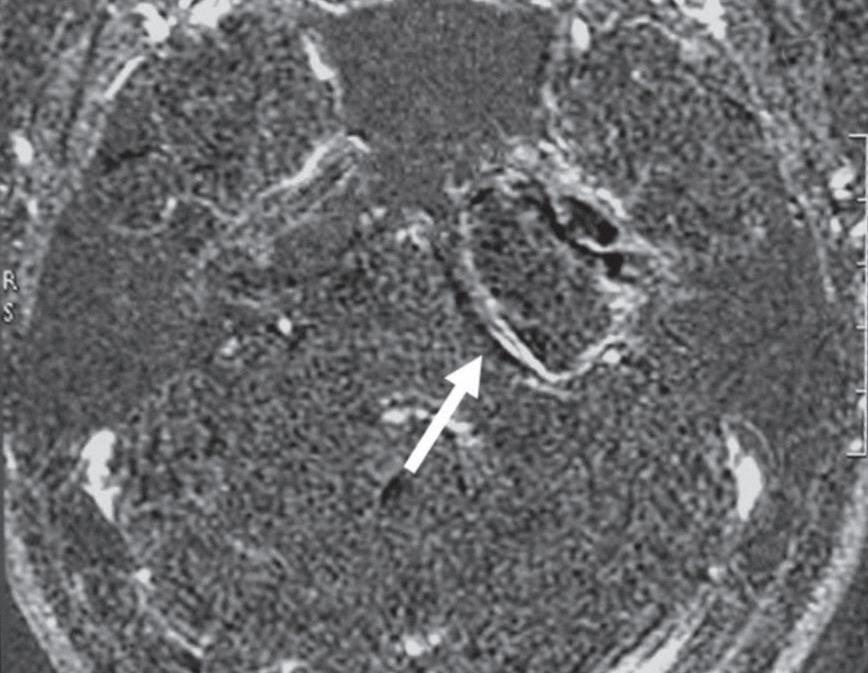

Fig. 1-16. Granuloma de colesterol no ápice petroso: RNM sequência axial T1 (a): lesão expansiva no ápice petroso, comprimindo a ponte, compatível com granuloma de colesterol, com sinal hiperintenso na sequência T1 (seta curta); liquor com sinal hipointenso (seta branca larga); gordura subcutânea com sinal hiperintenso na sequência T1 (seta preta longa). RNM sequência axial T1 com supressão de gordura; (b): a lesão persiste com sinal hiperintenso na sequência T1 com supressão de gordura (seta); liquor no quarto ventrículo com sinal hipointenso (seta larga); gordura subcutânea suprimida. RNM axial T1 com subtração das sequências pré e pós-gadolínio; (c): demonstra apenas áreas de impregnação pelo agente paramagnético, na periferia do granuloma de colesterol (seta). RNM axial T2; (d): lesão expansiva no ápice petroso com depósito periférico de hemossiderina, halo de sinal hipointenso (seta curta); liquor com sinal hiperintenso no quarto ventrículo (seta longa).